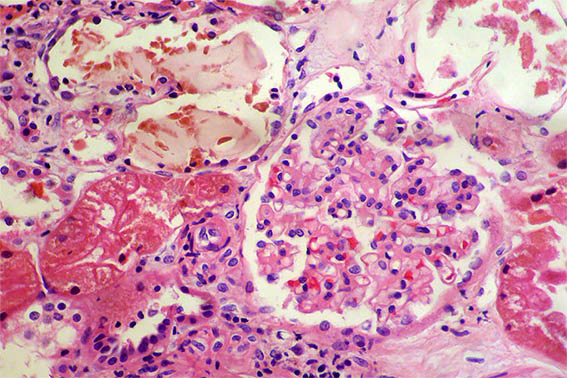

A 40-year-old man presented with severe acute liver failure secondary to hepatitis A virus infection, and acute kidney injury.

More relevant laboratory tests: thrombocytopenia (76,000), hyperbilirubinemia (7.1 mg/dL), transaminitis (1.830 U/L and 2.320 U/L), and elevated INR. Serum creatinine: 5.2 mg/dL, BUN: 78 mg/dL, proteinuria: 100 mg/dL, without microhematuria.

A kidney biopsy was performed. Look at the images.

Figure 4. H&E, X400.

Figure 5. H&E, X400.